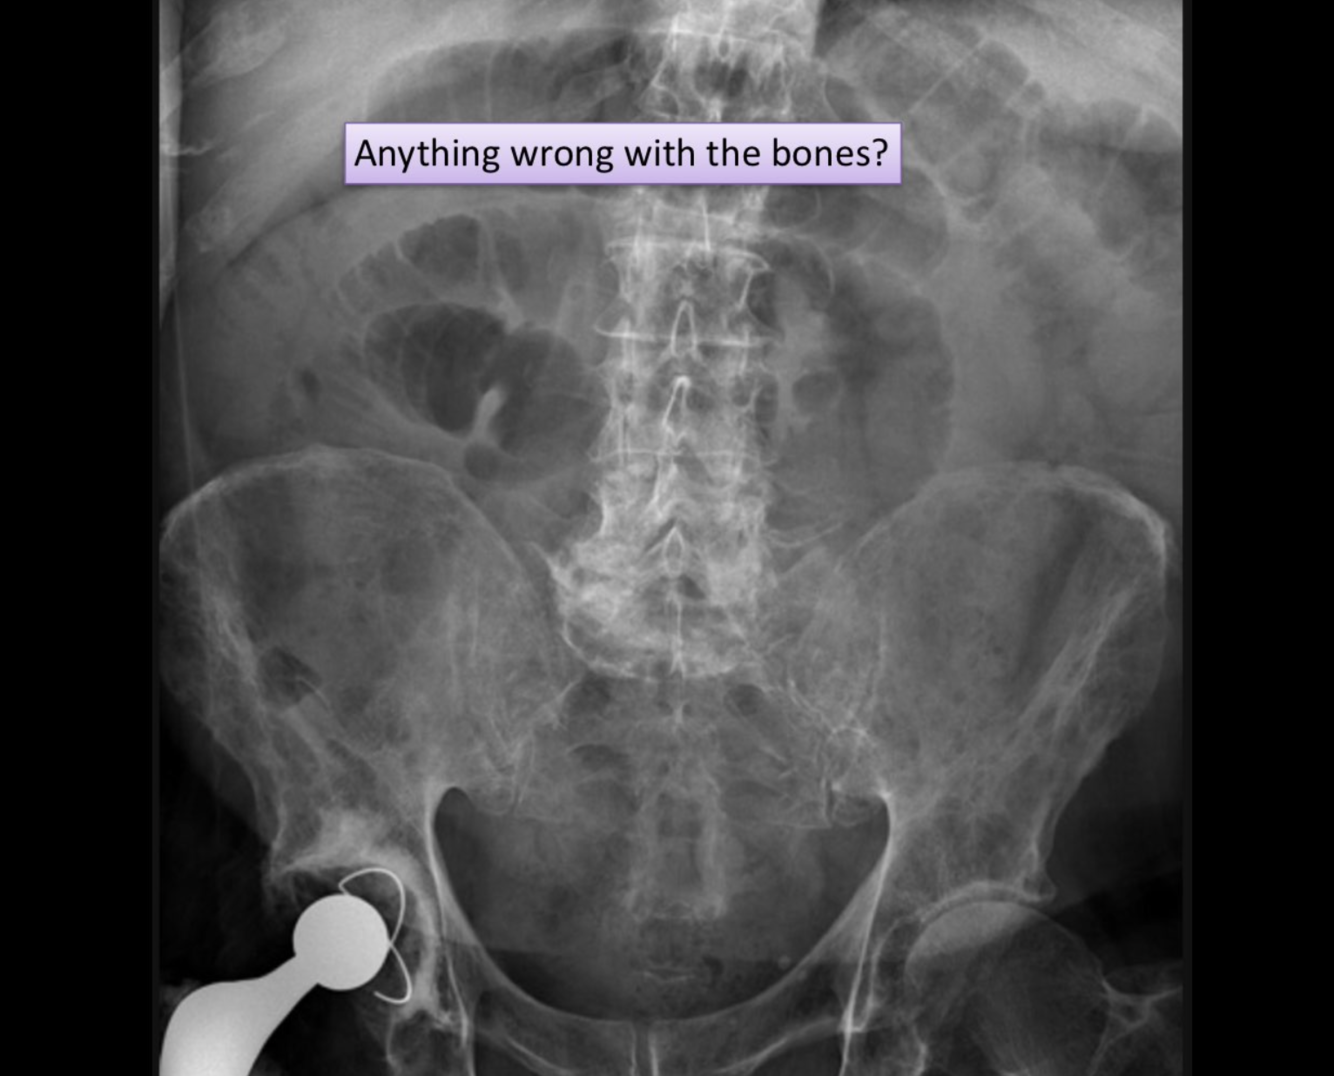

hyperparathyroidism